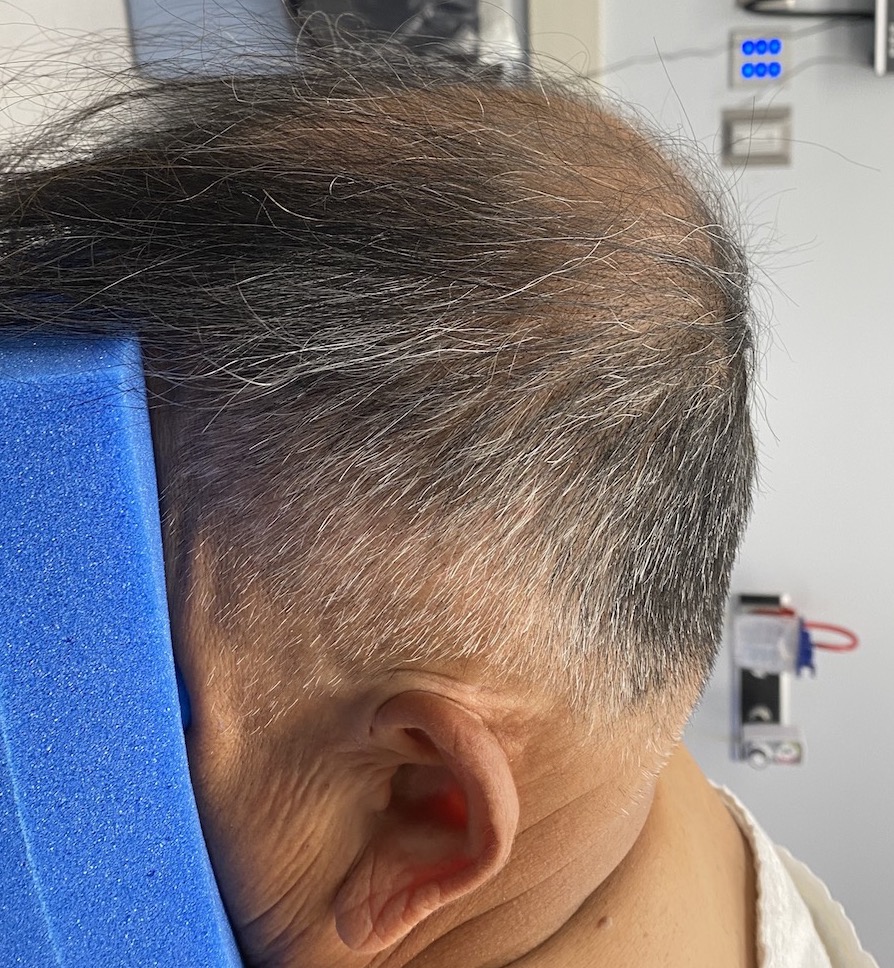

Desire for improved head shape that had bothered him most of his adult life.

Initial correction of his peaked head shape deformity with sagittal ridge reduction and a custom skull implant with a five year stable result.

Desire for improved head shape that had bothered him most of his adult life.

Initial correction of his peaked head shape deformity with sagittal ridge reduction and a custom skull implant with a five year stable result.